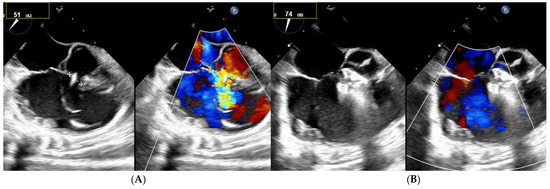

Among the 13 patients with multiple right-sided exits, 7 had no shunt during follow-up (Figure 2 and Figure 3). Among the five patients with both multifenestrated defects and Gerbode-type VSD, three achieved complete occlusion and the other two had tiny residual shunts. All the residual shunts were trivial shunts persistent at 1 and 6 months of follow-up.

Figure 3. Patient with multifenestrated PmVSD and Gerbode-type VSD. (A) Notice the large aneurysm with a basis of 9 mm on left side. (B) After implantation of 8–10 mm Konar device, no residual shunt is observed.